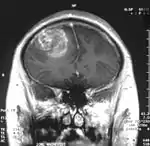

Глиобластома

Мультиформная глиобластóма (англ. Glioblastoma multiforme, GBM) — наиболее частая и наиболее агрессивная форма опухоли мозга, которая составляет до 52 % первичных опухолей мозга и до 20 % всех внутричерепных опухолей. Несмотря на то что глиобластома является наиболее частой первичной опухолью мозга, на 100 000 жителей Европы и Северной Америки регистрируется всего 2—3 случая заболевания[1]. Термин «глиобластома» подразумевает два варианта этой болезни: гигантоклеточная глиобластома и глиосаркома.